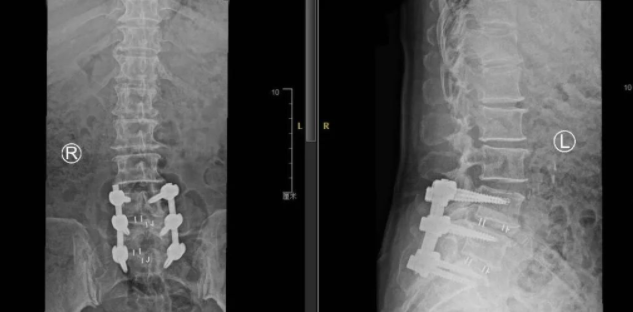

术后

在骨科机器人+3D裸眼显微镜的辅助下,李阿姨的手术进行的很顺利。这一切都与传统“开大刀”的手术方式形成极大对比——可以说,骨科机器人+3D裸眼显微镜在当今脊柱外科关于“微创手术”这一概念中,已成为一种趋势,其最大程度的保证了患者在术中的安全,将微创手术最为核心的“精准”、“伤害小”的特点完全展现,这对于患者本身及术后的康复来说都极为有利!